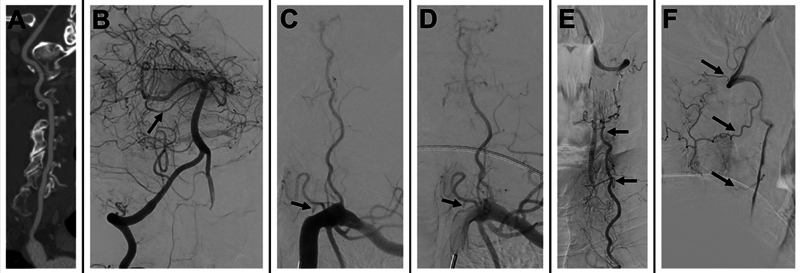

Unmasking vertebral artery stump syndrome in recurrent posterior strokes treated with endovascular therapy.